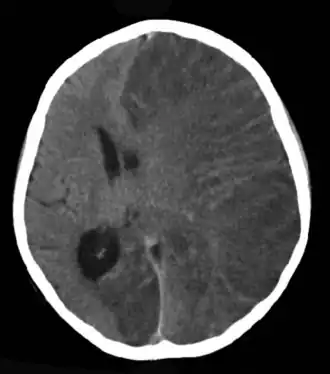

Por un proceso de epilepsia se entiende por el contrario una enfermedad-epilepsia, consecuencia de una enfermedad neurológica progresiva (proceso en continuación, no concluido). El ejemplo más importante y común en un proceso de epilepsia es el tumor cerebral, aunque también pueden conducir a una epilepsia los trastornos vasculares o enfermedades metabólicas. Puede ser una manifestación de la enfermedad de Wernicke.

La epilepsia así como las crisis epilépticas pueden en la actualidad recibir un tratamiento con resultados aceptables. En la mayoría de los casos, las epilepsias de la infancia se curan en la pubertad.[32] Cuando la epilepsia se debe a una lesión claramente visible y esa lesión es eliminada quirúrgicamente, se reduce la intensidad y frecuencia o bien, en muchos casos, se cura la epilepsia.[33] Por lo tanto, al comienzo del tratamiento se examina al individuo, en busca de causas de la epilepsia que se puedan eliminar, por ejemplo, la operación de un tumor cerebral o la supresión o mitigación de un trastorno metabólico.

La neurocirugía está indicada cuando la epilepsia es resistente a los AEDs. La cirugía puede ser paliativa o curativa. La paliativa se realiza en los casos de epilepsias catastróficas. La valoración de realizar una cirugía resectiva, que pueda ser curativa, debe realizarse antes del planteamiento de realizar tratamientos paliativos como la estimulación del nervio vago. Esta valoración tiene dos fases: una no invasiva y una invasiva; la no invasiva consiste en realizar estudios clínicos que no necesitan de una intervención quirúrgica. Estos estudios son: EEG basal, un video monitoreo, una IRM de cerebro con características especiales, de acuerdo con el tipo de epilepsia que se esté investigando. Pueden sumarse estudios de S.P.E.C.T. o de P.E.T. Siempre incluye además una valoración neurosicológica.[39]